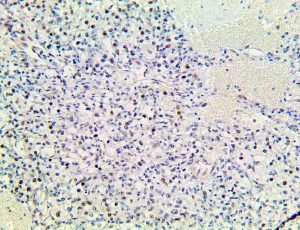

It is the ICU physician who is most likely to witness one of the deadliest manifestations of the abnormal immunological response, the cytokine storm syndrome (CSS). This response is also referred to by some as the cytokine release syndrome (CRS). CSS is characterized by continuous activation and expansion of macrophage and lymphocyte populations, which secrete large amounts of cytokines, causing the cytokine storm. This massive cytokine release is akin to hemophagocytic lymphohistiocytosis (HLH) disease, a syndrome characterized by initial unchecked and persistent activation of cytotoxic T lymphocytes and NK cells.

Clinical and laboratory manifestations of HLH include fever, enlarged liver and/or spleen, neurologic dysfunction, coagulopathy, liver dysfunction, cytopenias (i.e., low levels of erythrocytes, leukocytes, and/or platelets), hypertriglyceridemia, hyperferritinemia, hemophagocytosis, and eventually diminished NK cell activity as the immune system becomes progressively paralyzed. HLH can be familial (primary HLH) or secondary to another disease process (sHLH), such as rheumatic disease, in which it is referred to as macrophage activation syndrome (MAS, characterized by elevated ferritin).